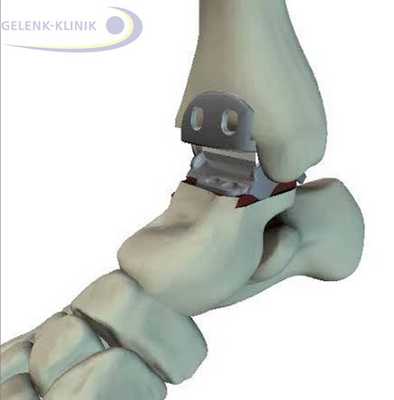

Артродез помогает восстановить безболезненность и потерянную подвижность. Данное вмешательство требует использования специальных винтов и интрамедуллярных гвоздей. Они фиксируют сустав до полной оссификации. © Gelenk-Klinik

Обездвиживание голеностопного сустава проводится под общим наркозом. Иногда используется и местная анестезия. Перед началом остеосинтеза, голеностоп освобождают от суставного хряща, то есть удаляют скользящий слой между суставными элементами голеностопа. Лишь после этой процедуры образуется прямой контакт между большеберцовой и таранной костями.

Прочное важное для остеосинтеза костное соединение, закрепляется при помощи винтов либо пластин. Артроскопические вмешательства подразумевают лишь микроскопические разрезы на коже. Сохранение мягких тканей является является важным элементов в таком лечении: только при низком рубцевании, в будущем возможно эндопротезирование.

Артродез голеностопного сустава проводится и при использовании интрамедуллярных гвоздей, которые соединяют большеберцовую кость с таранной и пяточной. Артроз нижнего голеностопа и тяжелые травмы пяточной кости требуют проведения данной методики. Применение интрамедуллярных гвоздей для обездвиживания голеностопа приводит ещё и обездвиживанию сустава между пяточной и таранной костью. © Gelenk-Klinik